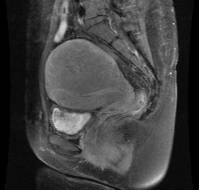

Ovarian pregnancies account for approximately 3% of all ectopic pregnancies. Second-trimester ovarian pregnancies are extremely rare. We report a case of ruptured ov..